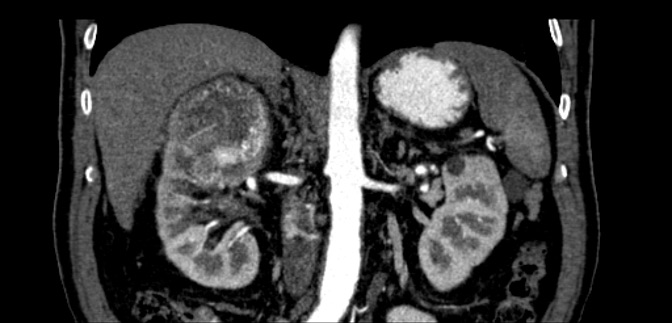

Η μάζα του νεφρού είναι ένα μόρφωμα (όγκος) που αναπτύσσεται στο νεφρικό παρέγχυμα και μπορεί να υποδηλώνει πολλές παθήσεις συμπεριλαμβανομένου και του καρκίνου.

Γενικότερα οι μάζες του νεφρού διακρίνονται σε καρκίνους και μη καρκίνους δηλαδή σε κακοήθεις και καλοήθεις βλάβες.